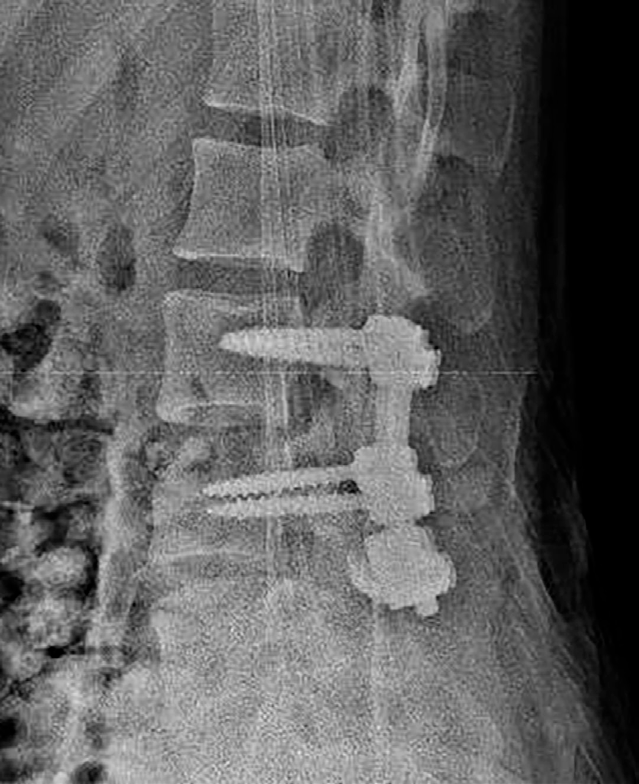

Tras 9 días de ingreso y comentar el caso con el equipo de columna para indicaciones al alta de cara a una IQ definitiva de la muñeca de manera diferida, se decide solicitar una RMN donde se informa una extensión de la fractura hacia los elementos óseos posteriores y disrupción completa del complejo ligamentoso posterior de L3-L4. En base a los nuevos hallazgos, se opta por estabilización de la lesión mediante fusión posterior instrumentada de L4 y L5 con aporte de injerto óseo.